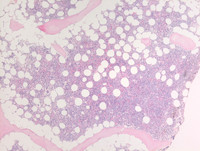

Figure 3: Marrow biopsy

Core biopsy is adequate for evaluation and is hypercellular for age with an estimated cellularity of 60% compressing scattered mostly normally megakaryocytes with very occasional dysplastic micromegakaryocytes with nuclear hypo-lobation and/or widely separated nuclei. There is preponderance of erythroid precursors (last image high power) which are maturing with intervening granulopoiesis including terminal segmented neutrophils and areas of abnormal localization of immature precursors (ALIP; third image bottom left). There is no morphologic evidence of lymphoma.

MDSRSMLDCore-biopsy

#00062010

#00062012

#00062011

#00062013